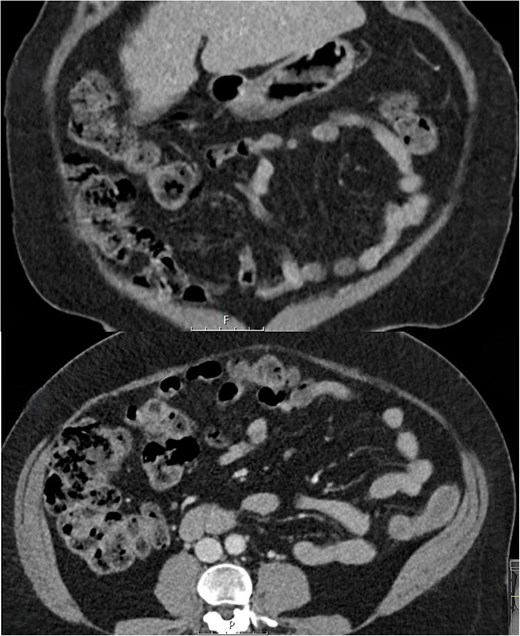

A woman in her 50s presented to the Emergency Department with a 1-week history of worsening right sided abdominal pain. Background included chronic back pain managed with long term methadone 100 mg once daily, and previous hepatitis C treated 9 years earlier with pegylated interferon and ribavirin. There was no history of vascular disease. She was taking lactulose 50 mL once daily to treat constipation secondary to methadone and described longstanding issues with abdominal discomfort, bloating, and frequent flatulence. She was living independently with her family, was an ex-smoker and previous IV drug user. On examination she was in some distress. Her vital signs were all normal. Abdominal examination revealed peritonism in the right abdomen. Blood tests showed normal inflammatory markers with a white cell count of 6.2 × 109/L, neutrophils of 2.8 × 109/L, and a C-reactive protein (CRP) of 6 mg/L. A CT abdomen was performed and was reported to show free air, which on review showed multiple subserosal and submucosal locules of air in the caecum and ascending colon, and a small volume of intra-abdominal free air with no free fluid. There were no other features to suggest ischaemia and no colonic diverticulosis (Fig. 1).

Coronal and axial CT slices showing pneumatosis in the right colon. Arrowheads demonstrate subserosal and submucosal gas.

The main differential diagnosis was between an acute abdomen with ischaemia of the right colon versus PC secondary to high dose lactulose. The degree of pain, patient distress, and localized peritonism with free air in the peritoneal cavity and air in the wall of the right colon was consistent with an acute abdomen. However, the normal vital signs and CRP of 6 mg/L suggested otherwise. The background of high dose lactulose, abdominal bloating and increased flatus, combined with the pattern of submucosal and subserosal air led to a provisional diagnosis of PC secondary to high dose lactulose being made. This resulted in a trial of medical treatment and avoidance of an acute laparoscopy or laparotomy.